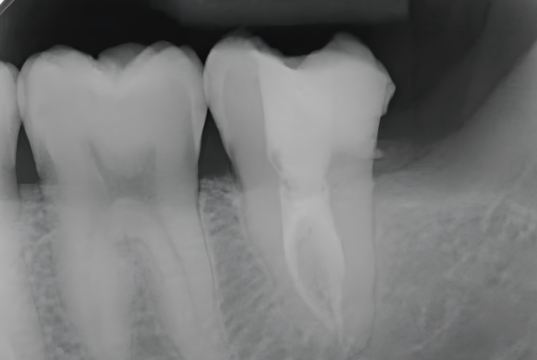

6. Post-Operative

A postoperative periapical radiograph was taken to evaluate the core build-up. The UltraCore dual-cure core build-up dental restorative materials exhibited excellent radiopacity, allowing clear visualization of its margins within the access cavity.

The tooth is now ready for a cuspal-coverage restoration as the next step to restore full function and long-term durability.